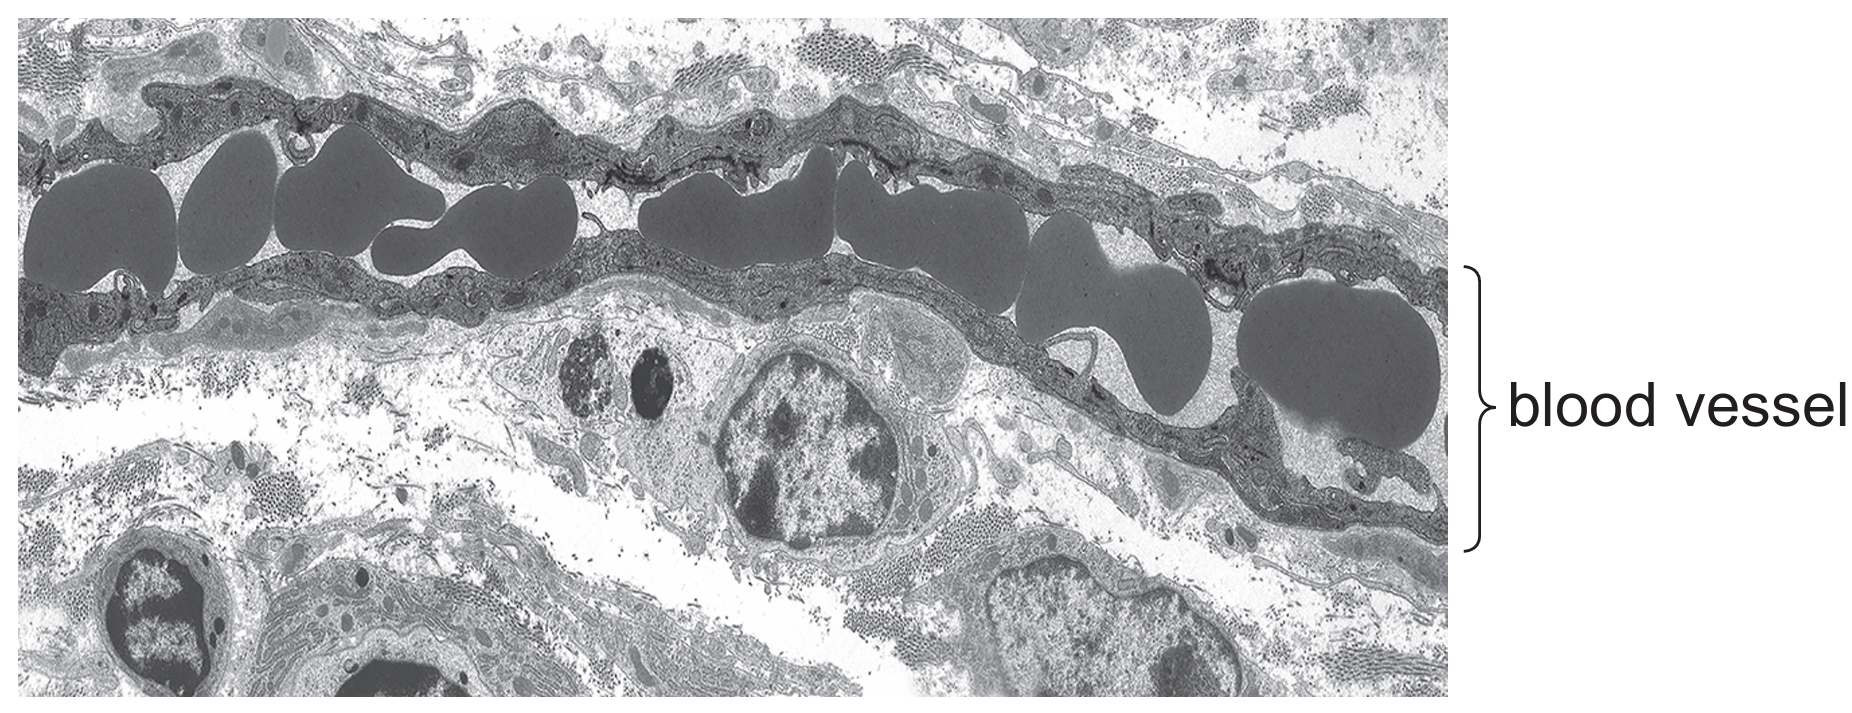

The electron micrograph shows a longitudinal section through a blood vessel.

Which type of blood vessel is shown?

The question refers to an electron micrograph (not shown here) of a blood vessel. Capillaries are identifiable by their single endothelial cell layer thickness (one cell thick), which allows for efficient gas exchange. Arterioles (A) and venules (D) have thicker walls, while veins (C) have valves.